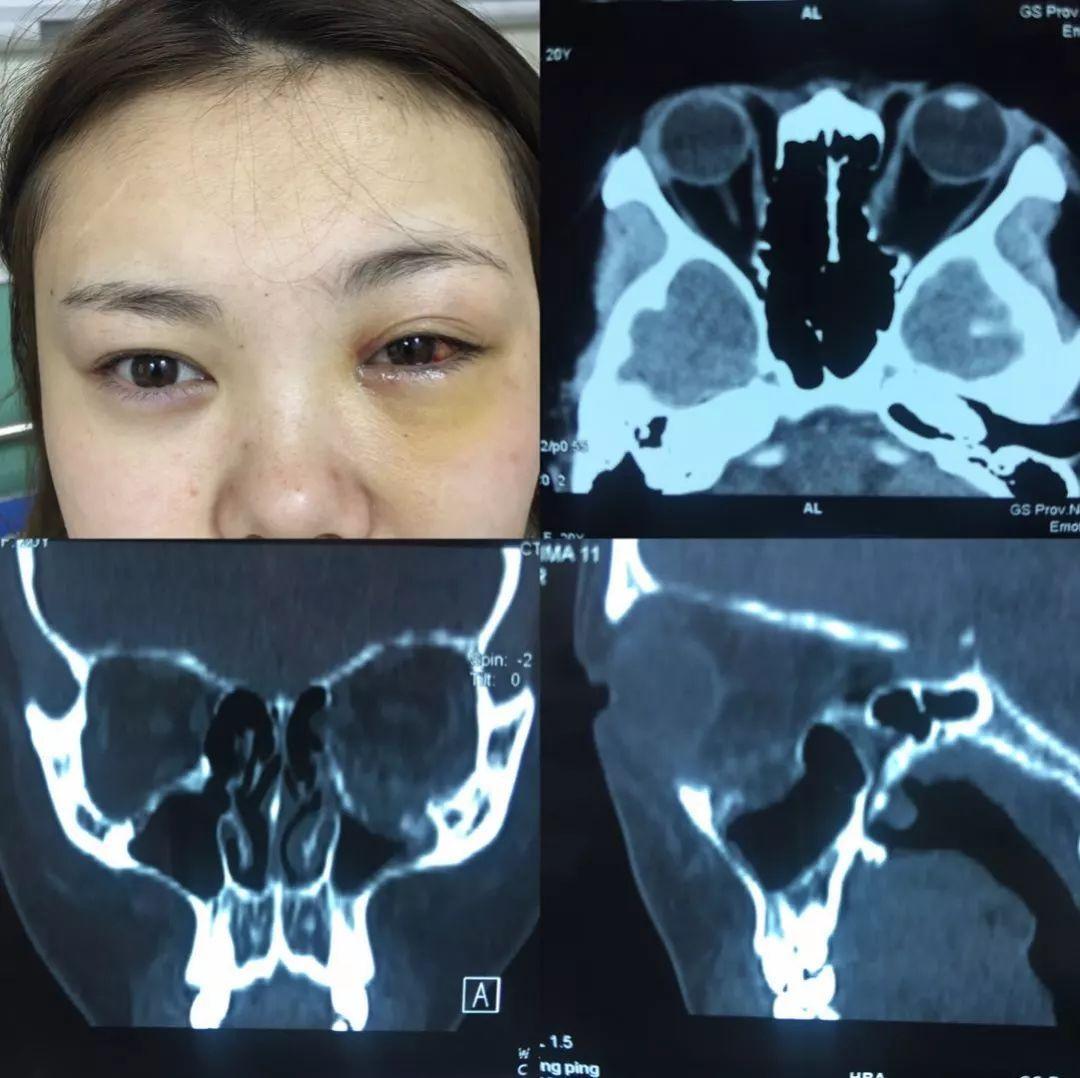

【病例讨论】双眼眶蜂窝织炎,原因?治疗? [病例帖]

图片尺寸2899x1925